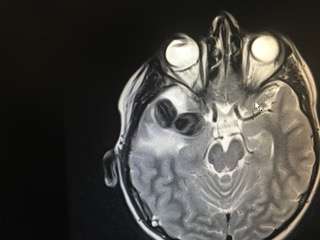

The Ericksons took their son back to the doctor, where Tate was diagnosed with a brain aneurysm. He underwent surgery but suffered a stroke that left him paralyzed on his left side and kept him in the hospital for another month.